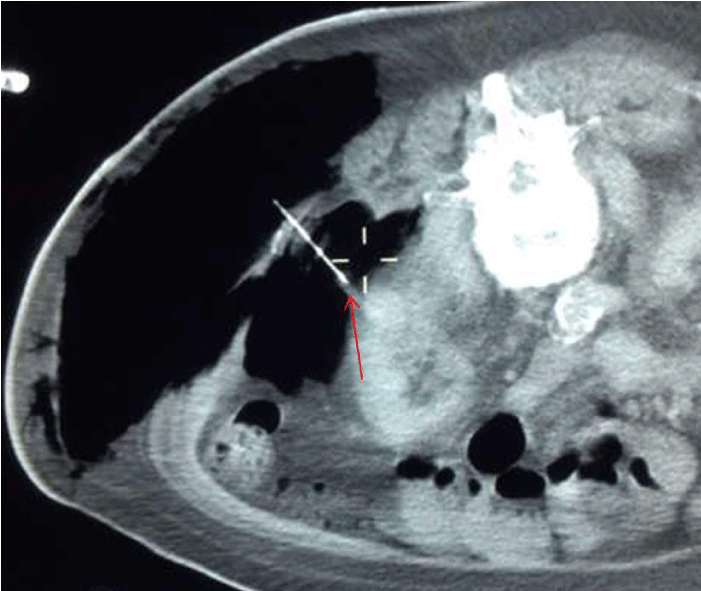

A 17- gauge, 20 cm Neuwave PR probe (NeuWave Medical, Madison, WI) was used for the procedure. After the probe was placed with its tip in the tumor via left posterolateral approach under ultrasound guidance (Figure 2), a CT scan to check position of the probe with tissue-lock revealed a large amount of air in the left flank subcutaneous tissues as well as left perinephric free air (Figure 3). The microwave ablation probe was immediately taken out of the patient. Using Seldinger technique with an 18-gauge needle, an 8 French pigtail drainage catheter was placed into the left flank subcutaneous tissues over an Amplatz guidewire (Figure 4) and the CO2 was aspirated. Subsequently, an 18-gauge needle was advanced into the left perinephric space under CT guidance and a small to moderate volume of the CO2 was aspirated. The ensuing CT scan demonstrated interval decrease in amount of CO2 in the left flank subcutaneous and left perinephric space. The subcutaneous pigtail drainage catheter was removed while the patient was still on the CT table.

Figure 3: Leakage of gas into the left retroperitoneal and subcutaneous spaces (cursor) during ablation with a 17-gauge PR probe (arrow). Note that the tip of the probe (arrow) is moved out of the lesion due to the gaseous expansion of the probe tract.